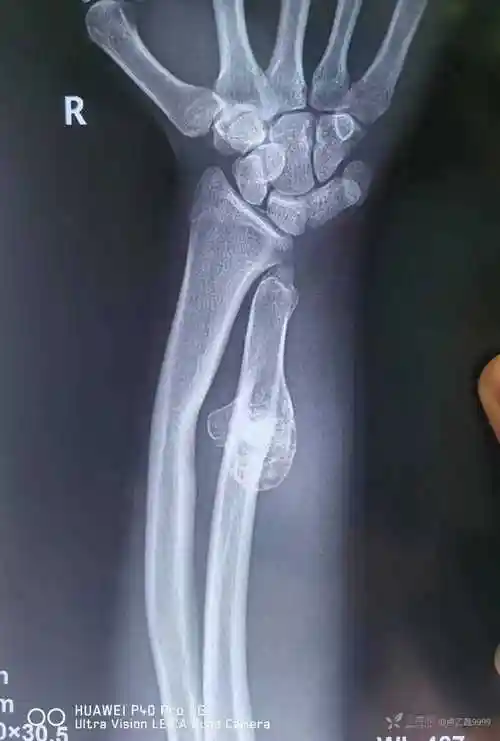

马德隆畸形

马德隆畸形(madelung deformity)的x线表现